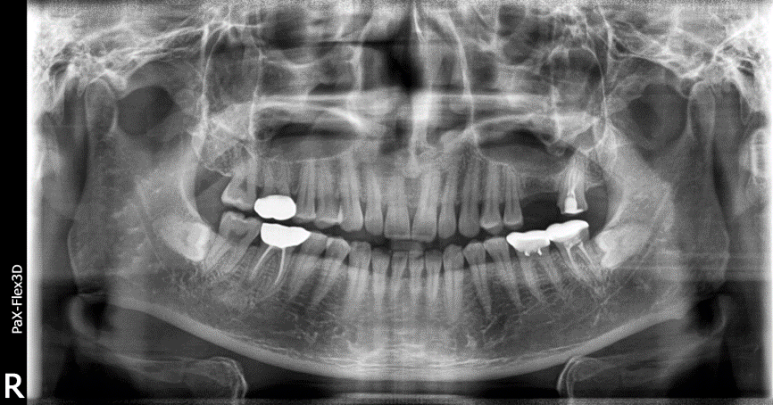

잇몸뼈 부족으로 상악동거상술을 통한 뼈이식 진행한 환자분의 x-ray